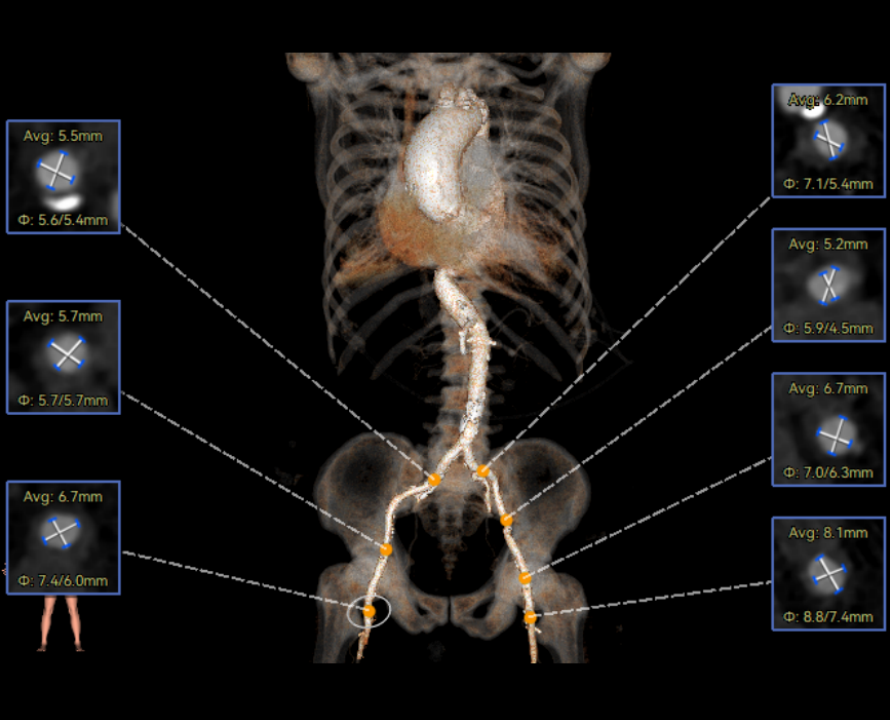

患者病史 主诉:发作性胸闷憋喘半年,加重伴呼吸困难2周。 现病史:患者半年前无明显诱因出现胸闷、憋喘,伴有下肢水肿,2周前上述症状明显加重,夜间不能平卧,痰中带血丝,为进一步诊治再次来我院,门诊以"心力衰竭"收入院。 既往史:肾功能不全、心房颤动 心脏超声提示:LVEF:0.54 1.主动脉瓣病变;2.主动脉瓣狭窄(重度)并反流(中度);3左室壁节段性运动不良;4.升主动脉扩张、双房扩大、左室肥厚;5.二尖瓣硬化并反流(中度);6.三尖瓣反流(轻-中度);7.肺动脉瓣反流;8.肺动脉高压(轻度)PGmean=105mmHg,Vmax=635cm/s,瓣口面积0.27cm²。 术前CT评估 Type0型二叶瓣,重度钙化,钙化集中在瓣叶游离缘,右冠窦为著;左冠高度11.8mm,由于左冠窦部空间较小,左冠风险较高, 升主动脉扩张,最宽处50.5mm;主动脉瓣环水平夹角61.5°,横位心。主动脉弓角77.6°,锐角弓,外周入路在腹主及髂总处有大量散状钙化,胸主处有81.6°的迂曲。 手术策略 推荐右侧股动脉为主入路,左侧股动脉为辅入路,送snare辅助过弯,使用18F大鞘,推荐预装ProStyle A® AV23瓣膜,20mm球囊预扩,初始定位对齐真实瓣环瓣上5mm超高位初始定位释放,释放过程中使瓣膜自然下滑,到工作位观察瓣膜形态,最终理想位置0-瓣下3mm。 手术过程 Step1:右侧股动脉为主入路、左侧股动脉为辅入路,成功穿刺并送入 18F 大鞘; Step2:主动脉根部造影,瓣口限制重 Step3:Type 0 型二叶瓣畸形合并重度钙化,患者瓣口狭窄严重,同时横位心,不仅导丝跨瓣困难,导管更难进入;术者凭借精湛操作,将导丝顺利跨瓣,反复微调导管角度,最终导管顺利过瓣。 导丝精准跨瓣 Step4:20mm球囊跨瓣困难,snare辅助下球囊成功跨瓣,预扩有腰无漏,冠脉充盈良好。 Step5: snare辅助下成功跨瓣,可以看到系统过弓形态瓣膜仓柔软,过弓顺滑 输送系统过弓 Step6:初始定位瓣上5mm开始释放,释放部分后观察瓣架下缘内收明显,后回收系统重新定位 初始定位 底部内收 Step7:瓣膜完全释放前,血压一度降低,术者迅速调整器械,实现瓣膜迅速锚定,快速释放 完全释放 Step8:20mm球囊后扩 最终造影,位置(瓣下3mm)形态良好 手术难点 患者不仅有主动脉瓣重度狭窄,还叠加肾功能不全、心房颤动等基础疾病,术中血流动力学波动极易引发心功能衰竭。ProStyle A® 预装干瓣“开包即用” 的特性压缩了术者操作时间,80%可回收设计给了术者容错空间,而这些看似难以逾越的难关,最终被团队精湛的医术一一化解,术中对于导丝、导管、球囊等器械每一步的精准操控,再到突发状况的从容处置,无不彰显着团队深厚的专业积淀与顶尖的操作技艺。 结语 此次手术的圆满成功,不仅彰显了陈玉国、李传保教授团队在复杂结构性心脏病介入治疗领域深厚的专业造诣与攻坚克难的决心,也充分验证了ProStyle A®系统在应对复杂高难度病例时的卓越适用性与有效性。 作为扎根齐鲁、享誉全国的医疗高地,山东大学齐鲁医院始终赓续着这片热土的仁厚文脉,将“医道从德,术业求精”的院训精神镌刻在每一次诊疗实践之中。特别是在结构性心脏病诊疗领域,医院团队始终怀揣医者担当,勇攀医学高峰,不断以更前沿的技术突破,为危重患者点亮重获新生的希望。 专家简介 陈玉国 山东大学齐鲁医院(点击查看专家详细简历) 李传保 山东大学齐鲁医院(点击查看专家详细简历) · END ·